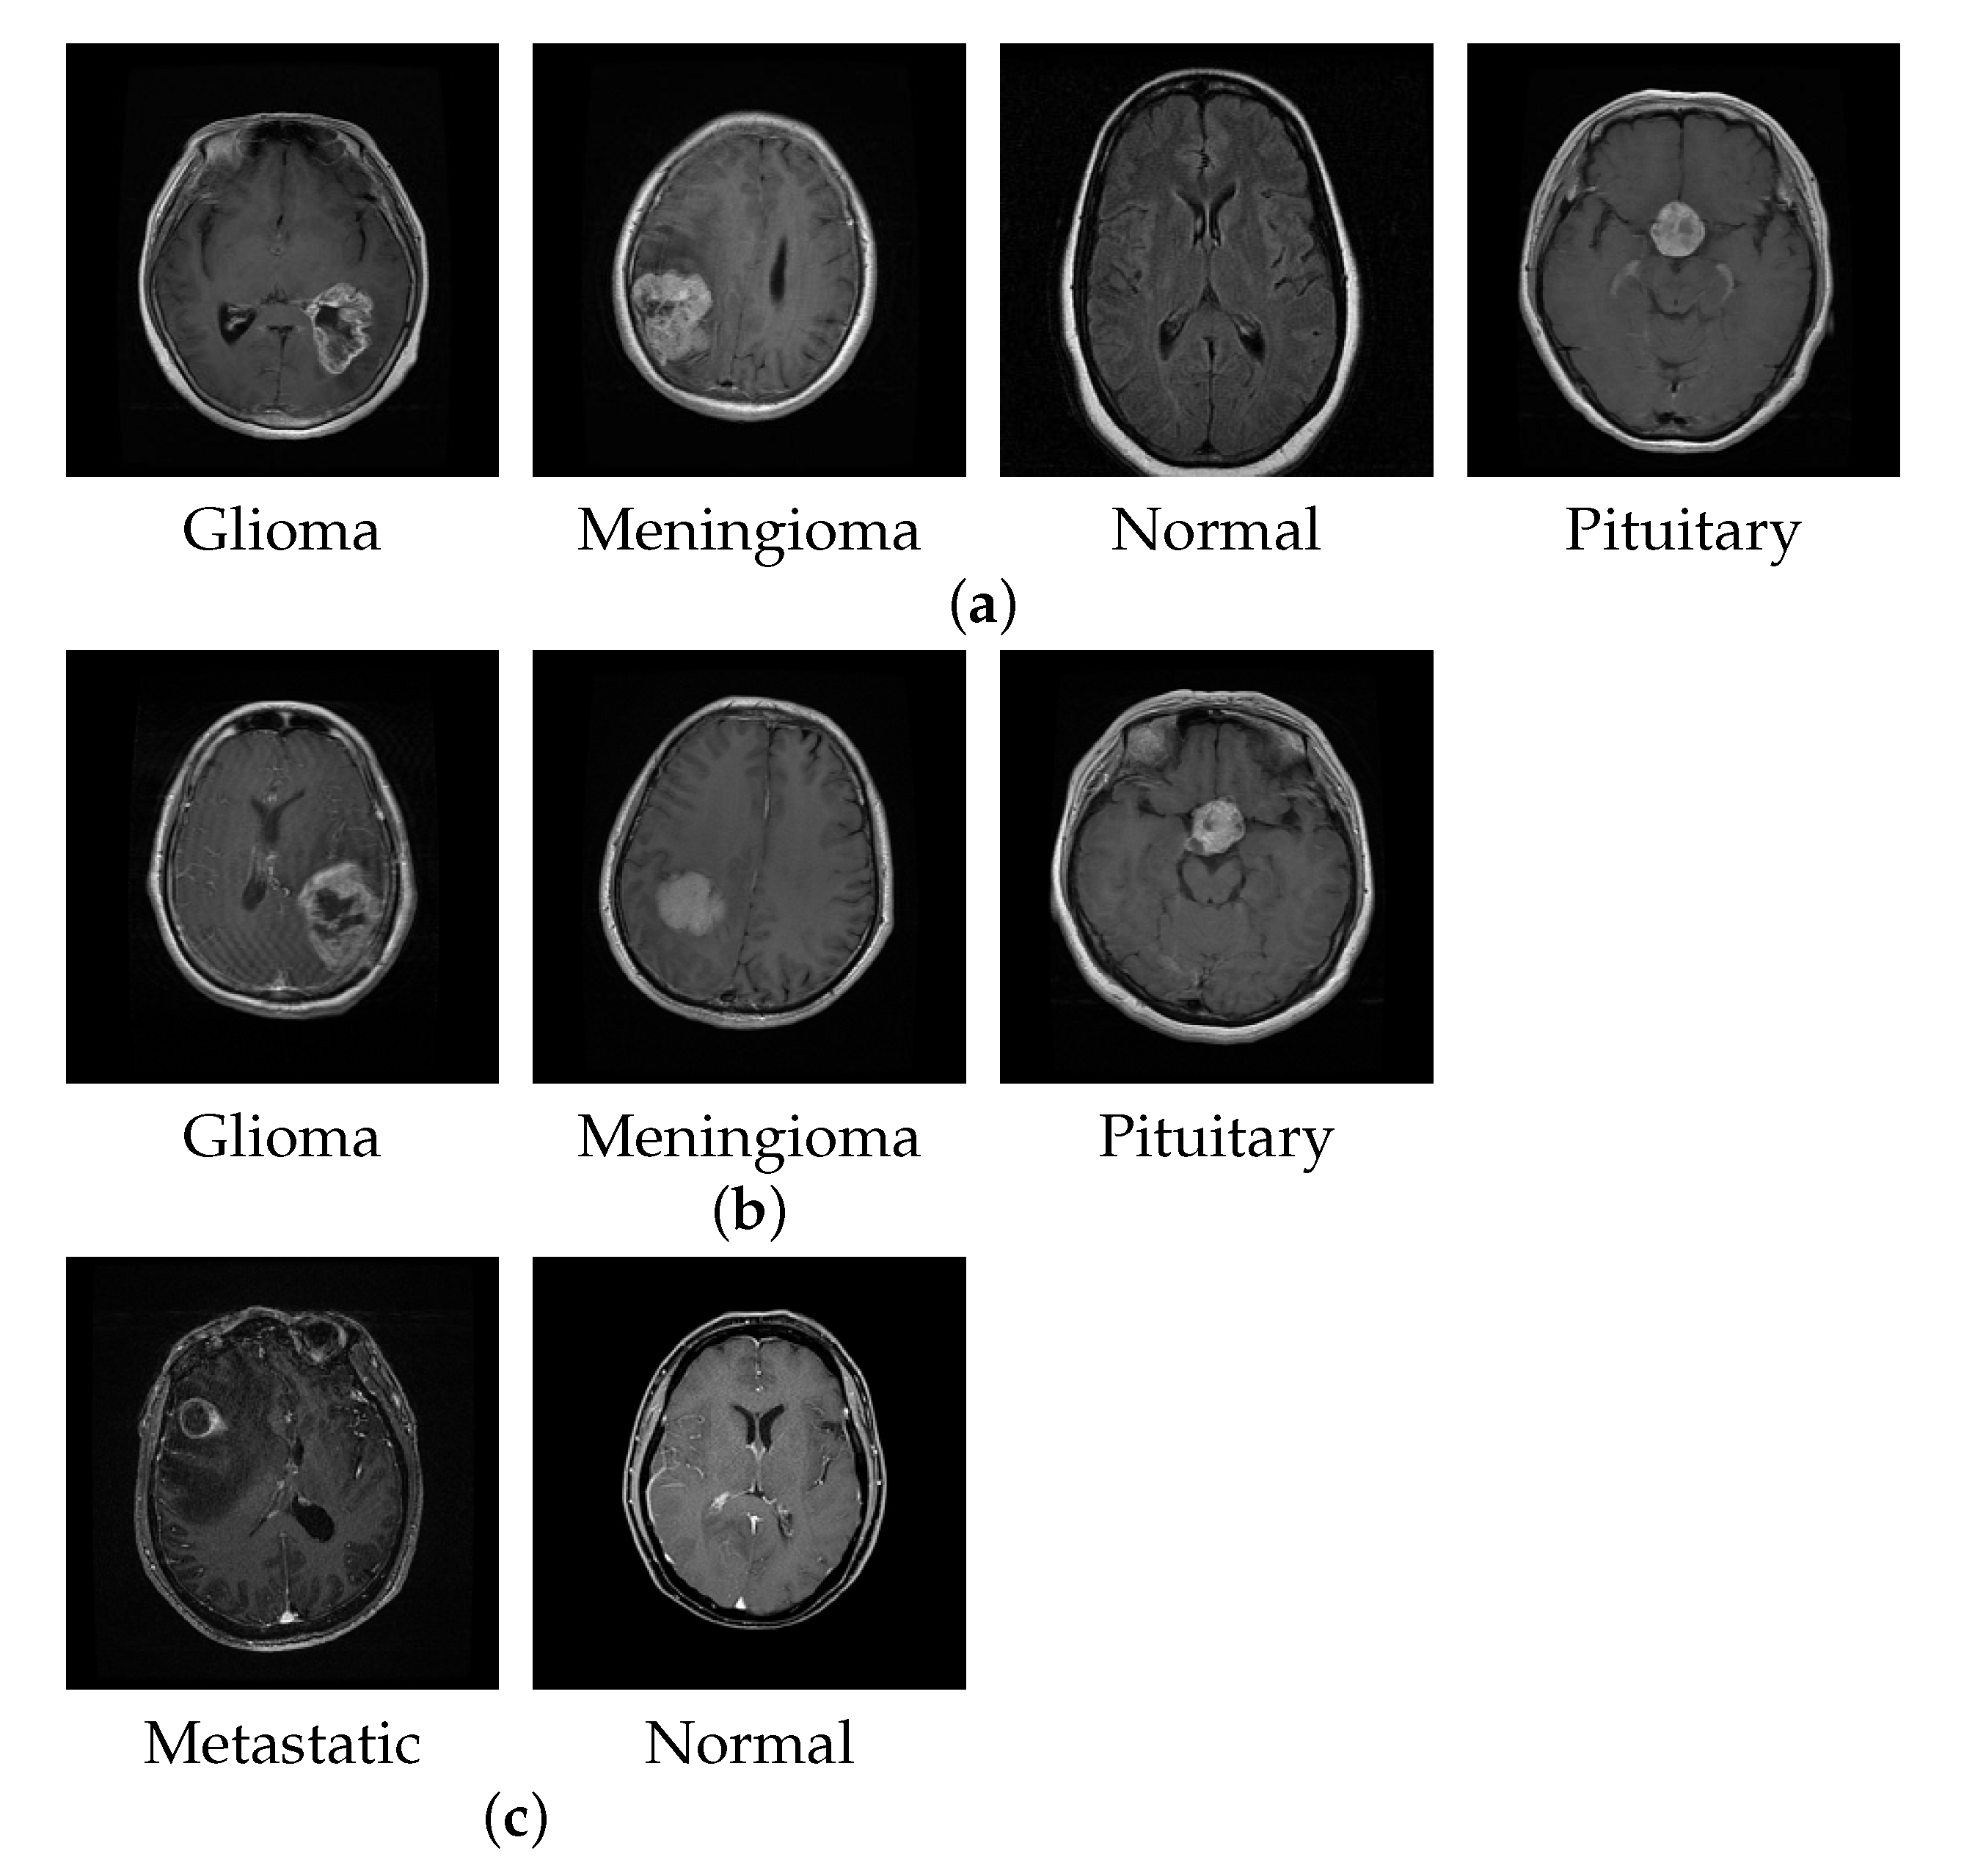

For brain tumor classification, we collected available MRI datasets from three different repositories to perform a set of experiments, as shown in Table 2. The first dataset is from the Kaggle website [53] and consists of multiple publicly available dataset repositories. The dataset comprises 3264 brain MRI slices divided into four classes: meningioma, glioma, pituitary, and no tumor, with slice numbers 937, 926, 901, and 500, respectively. We named this dataset BT-4C for simplicity. The second dataset is Figshare [54], which contains 3064 T1-weighted contrast-enhanced images from 233 patients. This dataset comprises three brain tumor classes: meningioma, glioma, and pituitary tumor, with slice numbers 708, 1426, and 930, respectively. We named this dataset BT-3C. The third dataset was collected in a private repository from Changzhou No.2 People’s Hospital in China in 2021. All image slices consisted of plain and dynamic enhanced MRI for metastatic tumor detection. We cleaned the data by approaching a doctor who examined all the MRIs manually. This dataset comprises 1109 slices, out of which 495 slices are metastatic tumor and the remaining 614 slices are normal without tumor. We named this dataset BT-2C due to it containing two classes. Figure 6 shows the examples of MRI brain images in BT-4C, BT-3C, and BT-2C datasets. In Section 4.2, the dataset is used for qualitative and quantitative analysis with the subdivisions of a training set, a validation set, and a test set. Of the dataset, 70% was for training, 15% was for validation, and the rest 15% was for testing. In Section 4.3, we conducted experiments with different partition ratios and cross-validation schemes to further test the performance of our proposed method. Additionally, for fair comparisons with the state-of-the-art works, we followed the same settings in the literature.

Figure 6.

The examples of brain MRI slices in different datasets. (a) BT-4C, (b) BT-3C, (c) BT-2C.